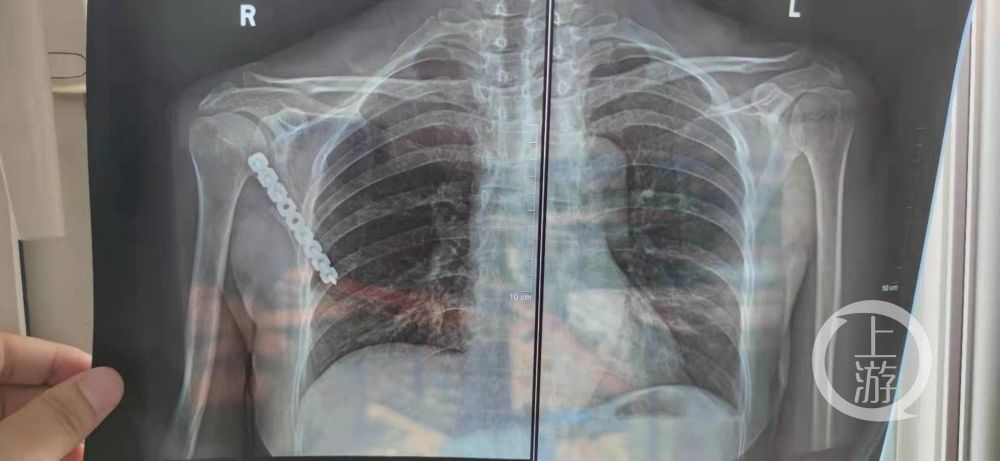

上游新闻采访人员注意到,舒女士左肩胛骨处被缝了13针,CT片显示,其右肩胛骨处安装了固定器械。

▲CT显示,舒女士右肩胛骨安装了固定器械,左边没安装。图片来源/受访者供图